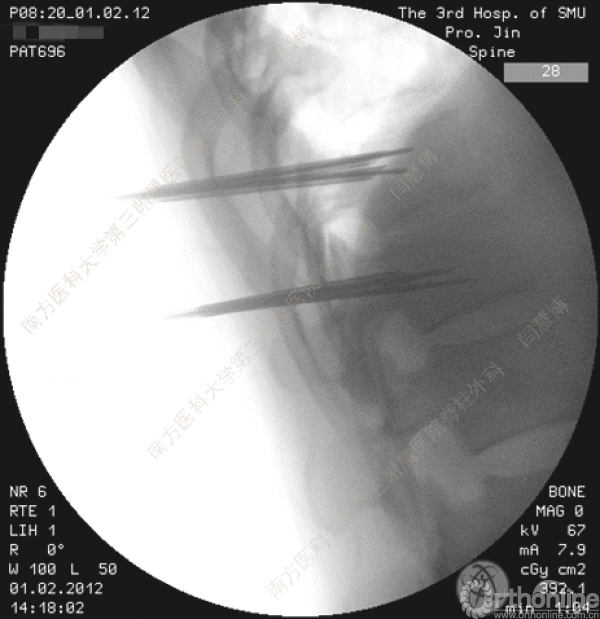

胸腰椎骨折是指由于外力造成胸腰椎骨质连续性的破坏,在如车祸、高处坠落等意外事故中,是最常见的脊柱损伤。老年患者由于本身存在骨质疏松,甚至有可能因为一些如滑倒、跌倒等低暴力因素导致胸腰椎骨折。胸腰椎骨折患者常合并神经功能损伤,且由于致伤因素基本为高能损伤,常合并其他脏器损伤,这为治疗带来了极大的困难和挑战。针对胸腰椎骨折,南方医科大学第三附属医院闫慧博教授介绍了他们运用微创方法治疗的经验。